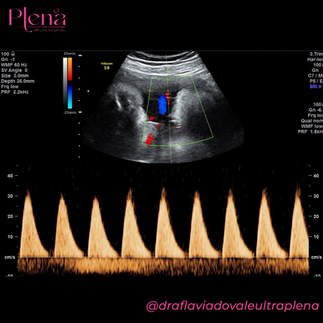

Exemplos de formas de onda de artéria umbilical inaceitáveis (a) e aceitáveis (b).

A gravação é aprimorada reduzindo a escala Doppler (ou seja, reduzindo a frequência de repetição do pulso) para ampliar a gravação da velocidade na tela, bem como ajustando a velocidade de varredura para cobrir apenas três a nove ondas consecutivas.

O PRF deve ser ajustado de acordo com o vaso estudado: um PRF baixo permitirá a visualização e medição precisa do fluxo de baixa velocidade; no entanto, produzirá aliasing quando forem encontradas altas velocidades. A forma de onda deve preencher pelo menos 75% da tela Doppler (consulte a Figura 3 ). (PONTO DE BOA PRÁTICA)